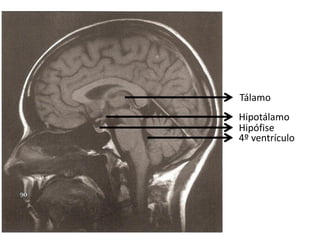

Ressonância Magnética do Crânio

• Sistema de obtenção de

imagens é mais sensível à

natureza molecular dos tecidos;

• Alta densidade tissular não

resulta em resolução de

contraste.

   Doenças da substância branca;

   Neoplasias;

   Doenças infecciosas;

   Distúrbios hemorrágicos;

   Distúrbios isquêmicos.

Tálamo

Hipotálamo

Hipófise

4º ventrículo